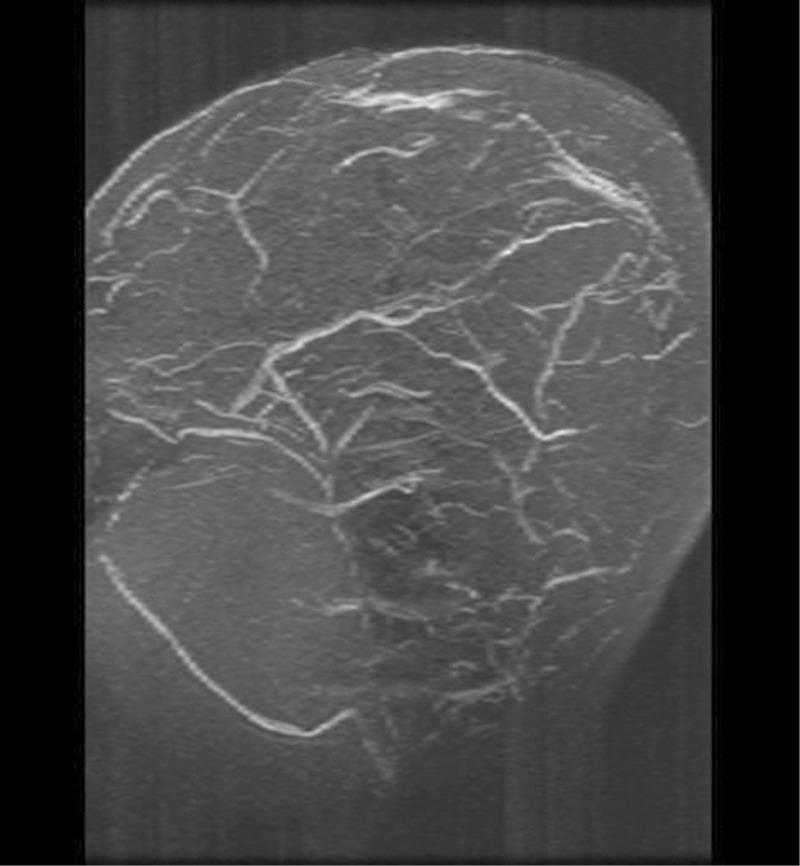

Cerebral venous sinus thrombosis (CVST) is a critical condition with significant morbidity and mortality. It primarily affects the young and healthy. CVST presents a diagnostic challenge due to its varied presentation patterns. We report the case of a 11-year-old boy diagnosed with CVST after presenting with a long history of continuous headache. He improved following anticoagulation therapy. Despite thorough investigation, no discernible underlying cause could be identified.

脑静脉窦血栓形成(CVST)是一种具有较高发病率和死亡率的严重疾病。它主要影响年轻人和健康人群。由于其临床表现多样,CVST在诊断上具有挑战性。我们报告了一例11岁男孩的病例,该男孩在出现长期持续性头痛后被诊断为CVST。抗凝治疗后病情有所改善。尽管进行了全面检查,但未发现明显的潜在病因。